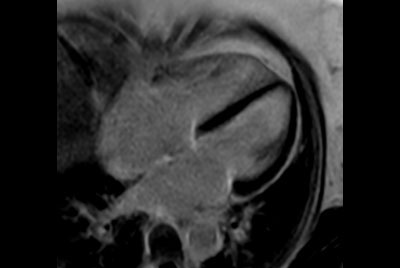

Fetal Cardiac with smart-sync